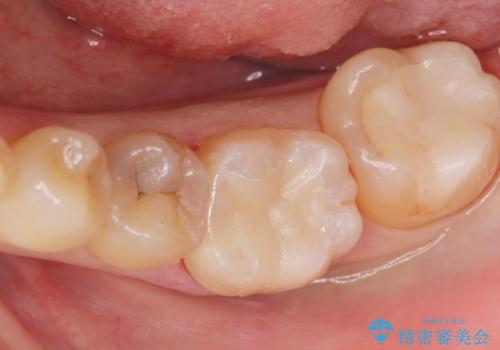

白い詰め物が入り患者様に満足して頂けました。

メタルインレーと比べてセラミックスのインレーは適合が良くて

虫歯の再発のリスクが少ないと言われています。